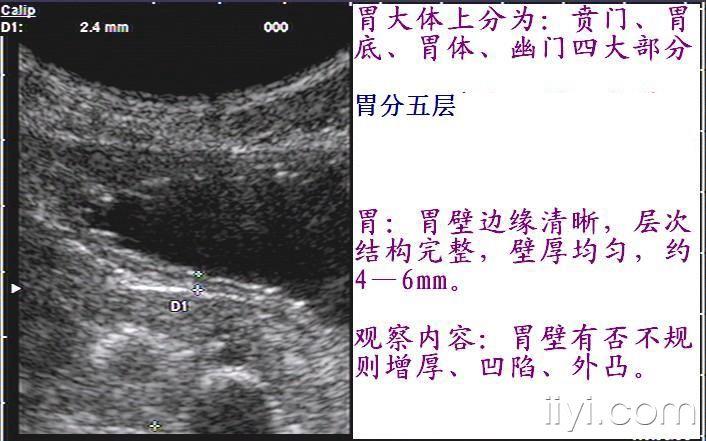

正常胃超声图像(10月8日更正)